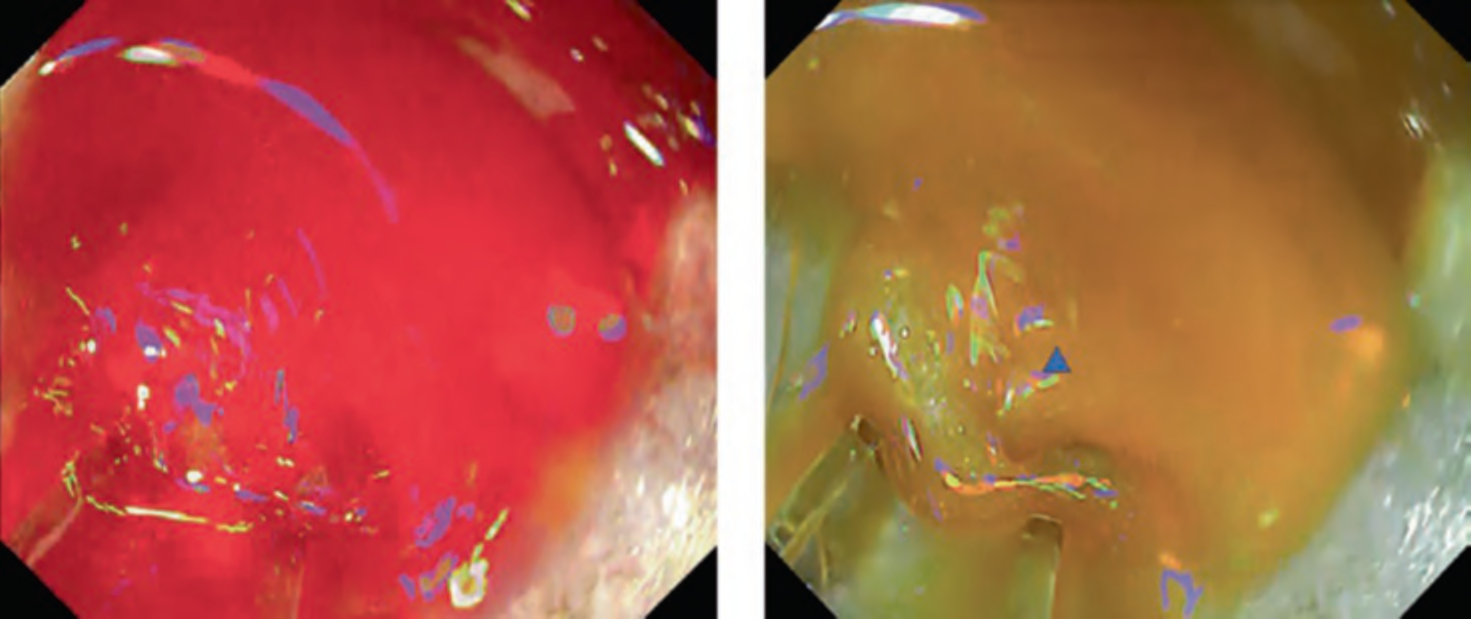

This mode is mainly aiming for identification of bleeding points. In cases of active bleeding, it is often difficult to continue the hemostasis because the pooled blood disturbs visualization. Potential usefulness of RDI in ESD by the improvement of identification of bleeding point has been reported [2–4]. A multicenter randomized controlled trial revealed significant reduction of endoscopists’ psychological stress during hemostasis even though it failed to show the shortening of hemostasis time [5]. There is also a case report of successful hemostasis for active bleeding due to peptic gastric ulcer [6] (Figs. 3, 4, and 5).

Fig. 5 Figure of spurting bleeding during duodenal endoscopic submucosal dissection. a White light imaging. b RDI mode 1